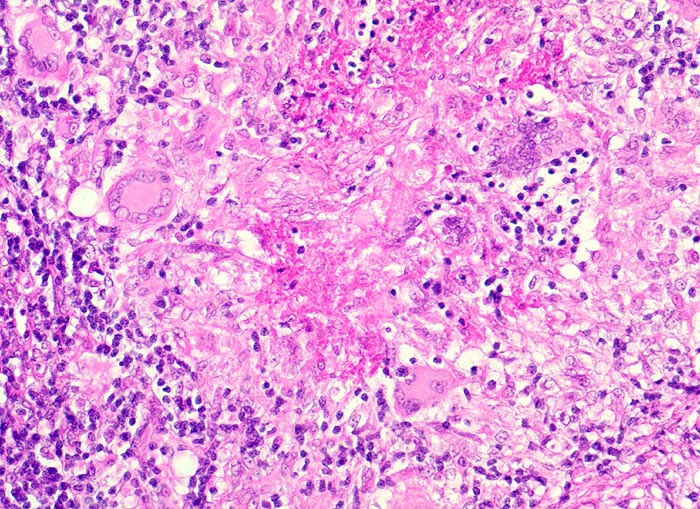

Basel 3BA HS/ Verkäsende Lymphknotentuberkulose

Verkäsende Lymphknotentuberkulose

• Lymphknoten mit ausgedehnten konfluierenden eosinophilen Nekrosezonen und nur wenig erhaltenem Lymphknotengewebe (blau).

• In den grösseren Nekrosearealen sind Kerntrümmer von neutrophilen Granulozyten erkennbar.

• Demarkierung der Nekroseareale durch schlanke Epitheloidzellen, Riesenzellen vom Langhanstyp mit hufeisenförmig angeordneten Kernen und Lymphozyten.

Bei der Tuberkulose sind meist verkäsende Granulome nachweisbar. Die atypische Mykobakteriose bildet lediglich angedeutete Granulome mit wenig Riesenzellen und keine oder minimale verkäsende Nekrosen. Bei immunsupprimierten Patienten finden sich grossleibige histiozytäre Zellen (> 3728), welche massenhaft säurefeste Stäbchen enthalten. Die histologische Unterscheidung von Mycobacterium tuberculosis und atypischen Mykobakterien gelingt jedoch nicht zuverlässig (> 726) (> 264). Für die definitive Diagnose ist der kulturelle Nachweis notwendig, welcher allerdings bei atypischen Mykobakterien sehr schwierig ist.